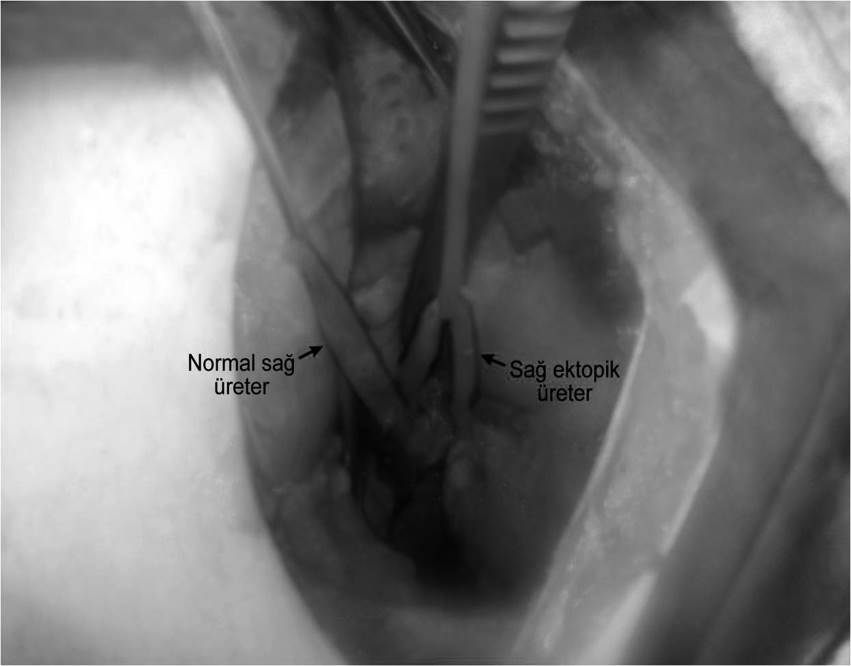

We aimed to present a rare case with right ectopic ureter (EU) occurred in different clivage and right double ureteropelvic system (DUS) which causes diurnal urinary incontinence (DUI) and serious social problem in a young girl accepted late period. A 14-years-old girl was evaluated for ectopic ureter causing urinary incontinence and recurrent infection. She had periodic pains in right lomber region and congenital urinary incontinence which repeated 5 minutes after toilet need. Her internal clothes were frequently wet. Hydroxyzine HCl, imipramin HCL, Sertralin HCL, desmopressin, and oxybutinin HCL had been used for the patient who applied to different health institutions. She did not have any benefits of these drugs. She had right ectopic ureter, associated with urethra and double collecting system in right kidney after performing renal USG, cystoscopy, VCUG, urodinamy, MRU, and MAG-3. Right ectopic ureter was found, dissected, and cut at the limit of urethra. Ureteroneocystostomy was performed. Vesicoureteral reflux was not identified in control VCUG. Postoperative evaluation documented no urinary incontinence and no low life quality. The patient has urinary continence, high life quality, and normal kidney function and she has no social problem. Ectopic ureter should be considered in the differential diagnosis of children and adolescents which applied with the congenital diurnal incontinence considering bladder dysfunctions treated with medical and conservative approaches.